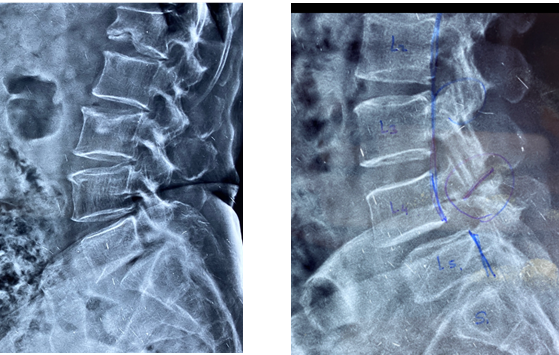

- Dynamic X-rays are usually diagnostic of spinal instability.